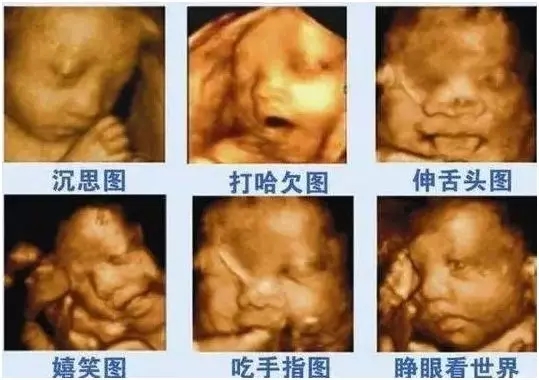

四维彩超能看到宝宝在肚子里的动作和表情,想把彩超的图像作为宝宝人生的第一张照片来收藏,首选四维彩超~

麻麻,我有点累了,换个姿势~

在妈妈肚子里最舒服了,我睡的很香哦!

宝宝在妈妈肚子里真的是生活的多姿多彩呢!